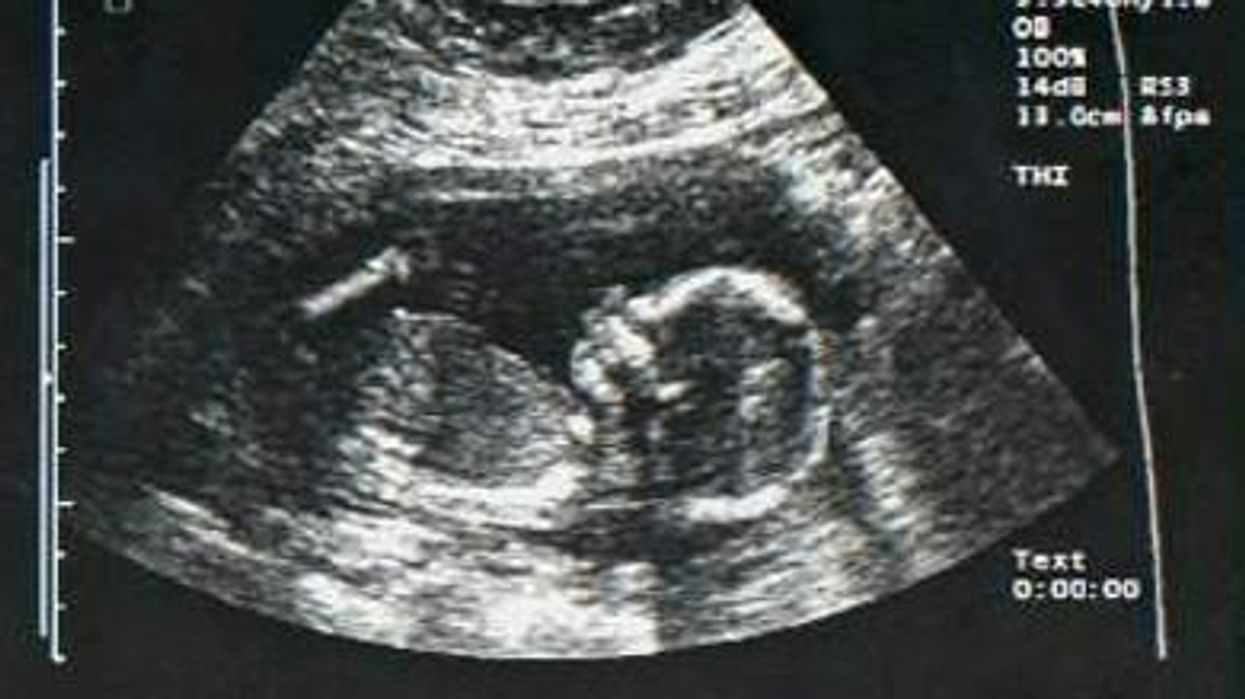

A hormonal treatment given to pregnant mothers who are at risk of giving birth to babies with ambiguous genitalia is raising concern among some researchers and gay activists because the treatment also decreases the likelihood that the baby will grow up a lesbian, the Los Angeles Times reports.

The treatment, which is called prenatal dexamethasone therapy and is only given to a few dozen women every year, is a step toward "engineering in the womb for sexual orientation," says Alice Dreger, an opponent of the treatment and a professor at Northwestern University.

"Most clinicians speak about this treatment as ambiguous-genitalia prevention," Dreger says. "Others suggest that you should prevent homosexuality if you can. But being gay or lesbian is not a disease and should not be treated as such."

In the face of criticism from Dreger and others, such as the National Center for Lesbian Rights, a consortium of medical groups will release updated guidelines for the treatment in September. The updates are expected to describe the treatment as experimental and reiterate that the standard approach for cases of ambiguous genitalia is to perform corrective surgery.